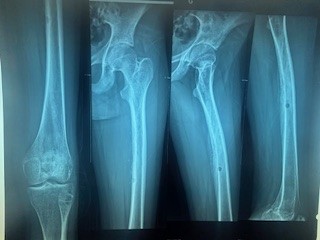

Pancreatic Metastasis as the Initial Presentation of a High-Grade Femoral Osteosarcoma in an Adolescent: An Exceptional Case Report”

Fatima Ezzohra ELHANAFI, Khadija Saadi, Sara OUASSIL, Meriem ELBAZ

A Case Report | 16 Jan 2026

Pancreatic Metastasis as the Initial Presentation of a High-Grade Femoral Osteosarcoma in an Adolesc...